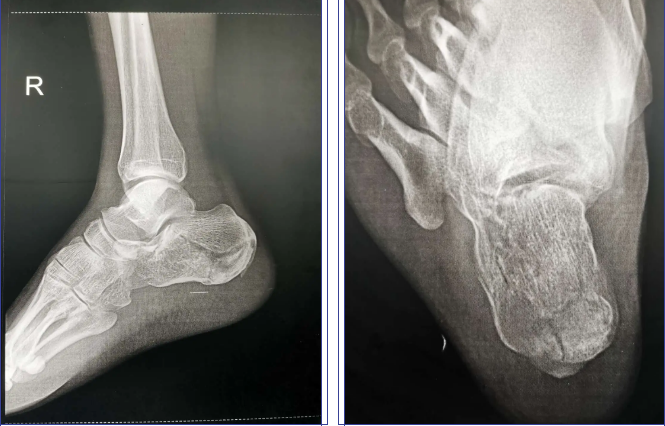

踝,x光片,跖骨,跟骨,手舟骨

跟骨骨折关节镜下微创治疗

10岁小孩跟骨x光片

小孩跟骨正常x光片

正常跟骨x片